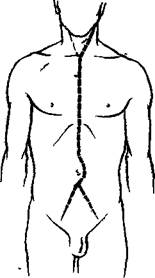

Прозектор становится справа от трупа и сохраняет ату позицию во все время вскрытия. Левше удобнее стоять слева от трупа (рис. 26).

Малым секционным ножом делают основной разрез (рис. 26) от подбородка до лобка по срединной линии, обходя пупок с левой стороны трупа, чтобы не повредить круглую связку печени. Секционный нож при этом нужно держать горизонтально, захватив рукоятку его в ладонь, и резать не концом, а брюшком лезвия (см. рис. 2 на стр. 23).

| Рис 26 Основной разрез стенки туловища. |